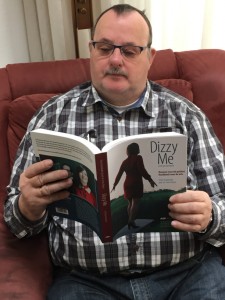

Jaaaaaa daar is ie dan. Het lang verwachte boek Dizzy Me.

Wat is het een spannende periode geweest vanaf de crowdfunding tot de uitgave van deze editie. Bloed, zweet en tranen, maar de auteurs van de Engelse editie van Dizzy Me, Tania en Floris, zijn erin geslaagd om een meesterwerk neer te zetten. Een handzaam boekwerk boordevol met actuele informatie. Een boek die thuishoort op de boekenplank van iedere KNO- of NPO-arts, waar ook ter wereld. Ze moeten er ook natuurlijk kennis van nemen, niet er alléén in ‘neuzen’. Medische studenten in opleiding moeten het als standaard werk bij zich hebben. Als dit allemaal gerealiseerd kan worden ziet de wereld van een patiënt, die een evenwichtsstoornis heeft, er een stuk evenwichtiger uit.

Ik kwam in 2015 de Nederlandse editie van dit boek op het spoor.

Door het lezen van het boek Dizzy Me kwam ik er achter dat men bij het UZA te Antwerpen ver waren m.b.t. het onderzoeken naar evenwichtsstoornissen en het stellen van een juiste diagnose. Ik heb toen gevraagd om mij door te verwijzen naar het UZA, alwaar ik werd geholpen door professor dr. Floris Wuyts. Na onderzoek en gebruikmakende van de SO STONED methodiek stelde de professor bij mij de diagnose Vestibulaire Paroxysmien (VP). Door het innemen van de medicatie Carbamazepine zijn de evenwichtsstoornissen drastisch afgenomen. Het is de bedoeling dat ik in het voorjaar van 2017 de medicijnen ga afbouwen en weer een bezoek aan professor dr. Floris Wuyts ga brengen.

Het is van groot belang dat de patiënten en medici kennis gaat nemen van het boek Dizzy Me. Er lopen te veel patiënten rond in de wereld die een misdiagnose hebben en eerder zieker worden dan beter.

De Engelse versie verschijnt juni van dit jaar, evenals een Engelse E-book. Later dit jaar verschijnt er ook een Spaanse uitgave.